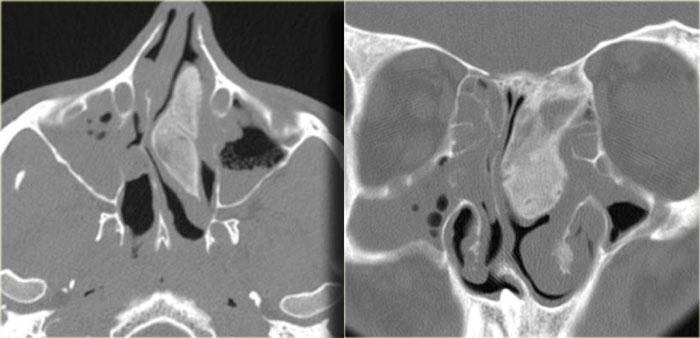

Bên trái là một trường hợp ban đầu được chẩn đoán nhầm là khối u.

Có vật chất tăng tỷ trọng ở xoang sàng sau bên phải, các ngách bướm-sàng hai bên, xoang bướm và có sự xâm lấn vào xương nền sọ (clivus).

Tình trạng tăng tỷ trọng là dấu hiệu tiên lượng tốt, gợi ý một quá trình lành tính.

Đây là ví dụ điển hình của viêm xoang nấm dị ứng.

Thông thường tổn thương này có vị trí ở phía trước hơn.

Bên trái là một ví dụ khác, điển hình hơn, của viêm xoang nấm dị ứng.

Có hình ảnh mờ đục hai bên hốc mũi, thường là dấu hiệu của quá trình viêm hoặc polyp.

Lưu ý hình ảnh phân lớp đồng tâm xen kẽ giữa tăng tỷ trọng và giảm tỷ trọng trong các xoang hàm.

Tình trạng tăng tỷ trọng là do dịch tiết đặc quánh và các thành phần nấm.

Tình trạng giảm tỷ trọng phản ánh các nang, bệnh lý niêm mạc và mô hạt.

Ở vùng xoang sàng, một phần tình trạng tăng tỷ trọng phản ánh viêm màng xương và tân tạo xương dọc theo các vách ngăn.